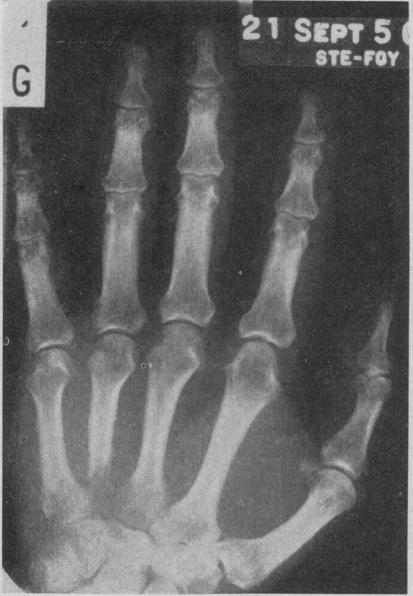

GRANDBOIS J

Can Med Assoc J. 1958 Nov 15;79(10):828-32.